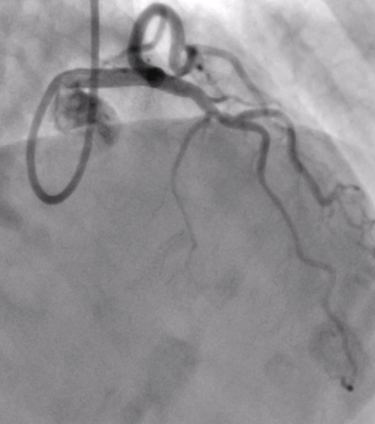

Invasive Angiography with Physiology & VasoReactivity tests

Advanced & Guidelines-Indicated State-of-the Art Invasive Diagnostics